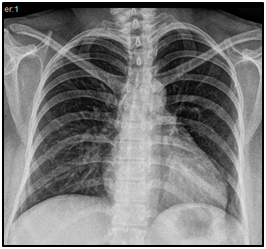

Acid-base balance without apparent complications ph: 7.41, pO2 43, pCO2 31, HCO3: 19, laboratories (Table 1), Tele chest (figure 2), electrocardiogram (figure 3), echocardiogram (figure 4). The abdominal route is interrupted under epidural anesthesia. Pregnancy with the following findings obtaining on 04-03-2020 at 11:29 hrs. R.N. female weight 2120g, size 44cm. APGAR 5/7, Capurro 34 SDG. After a surgical event, she admits to the ICU as multidisciplinary management; oxygen supplementation starts, and the latter prophylactic low-molecular-weight heparin, after four days of ICU treatment with favorable evolution, is admitted to the gynecology floor to begin cardiac rehabilitation and continuous monitoring, thus progressing correct deciding discharge from the service.

Figure 2 A.P. chest tele with a slight increase in the bronchoalveolar weft.